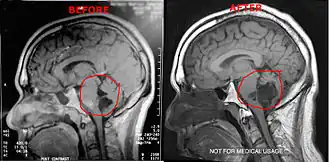

Magnetic resonance imaging (MRI) and computed tomography (CT) brain scans can be used to identify these tumors.

Treatment to remove these tumors always involve radical surgery. The reported recurrence rate for a subtotal removal is 30% after a mean interval period of 8.1 years.[4] Surgery is the primary treatment for removal of the brain tumor. Use of an endoscope may assist on obtaining a more complete surgical removal from hidden recesses.[5]

It has been seen that a few patients have tumors that grow unusually fast, especially after surgery. After surgery it is highly suggested the patients get quarterly MRI's to monitor their tumors or as per neurosurgeons/neurologists order. If monitoring the tumor, it is suggested to use the same facility for each scan. Using different facilities can result in minor variations in the scan which can result in false measurements of the brain tumor.